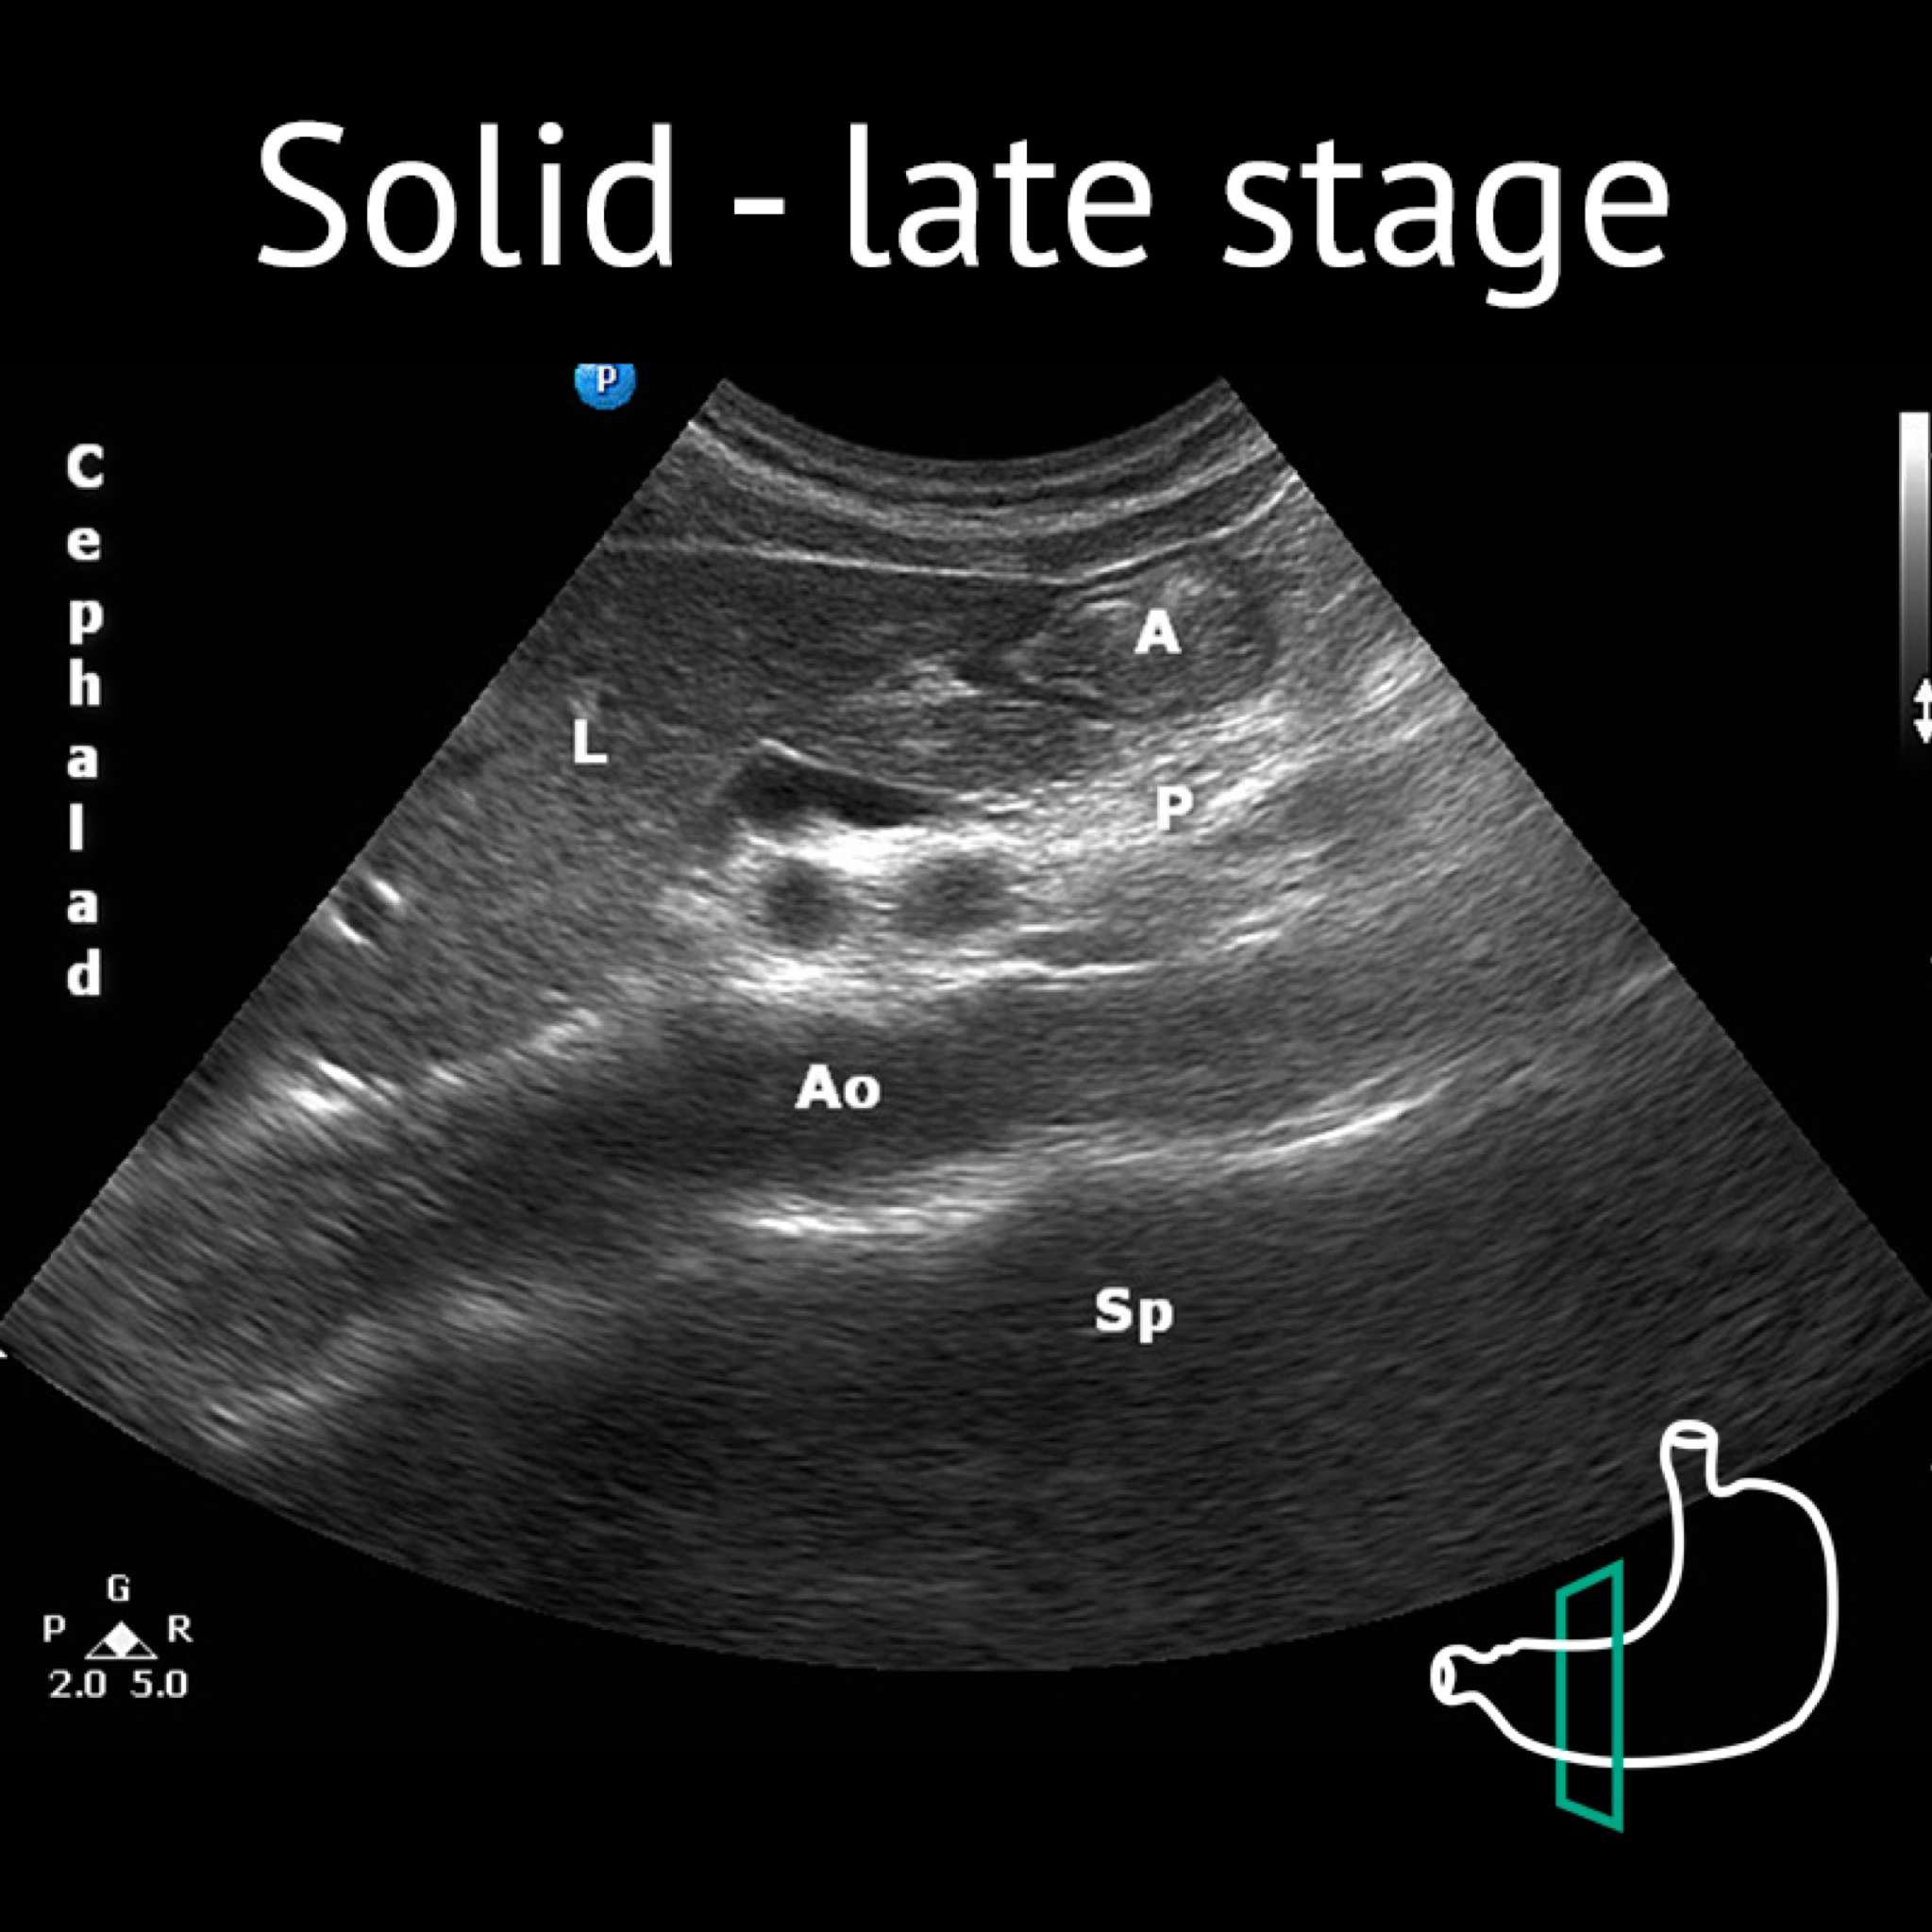

A: antrum; Ao: aorta; L: liver; P: pancreas; Sma: superior mesenteric artery; Sp: spine